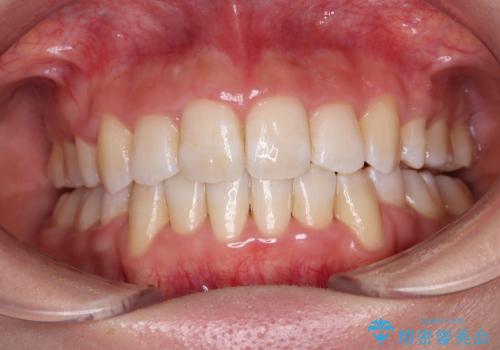

矯正歯科治療 → 上下顎前突(口ゴボ)

- デコボコと口元の突出感を改善 抜歯矯正治療